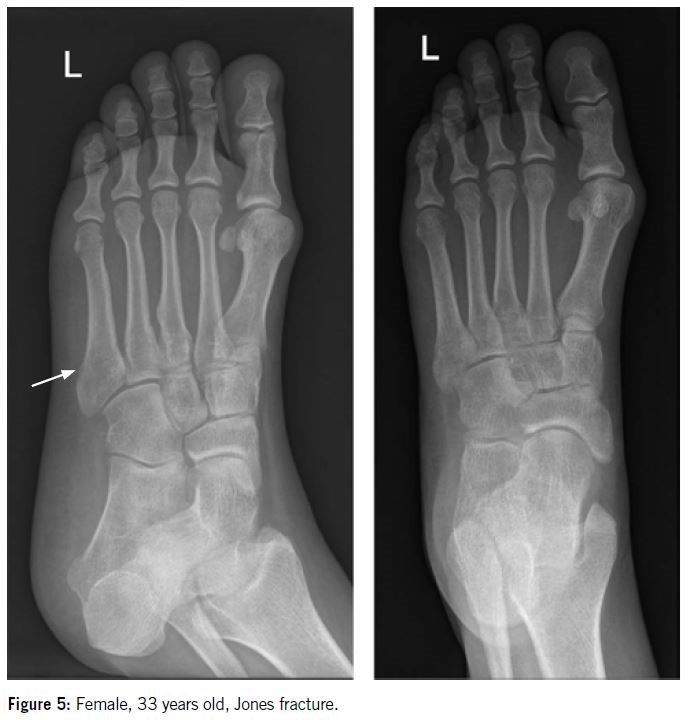

The Lawrence and Botte classification system (Figure 3) is commonly used and holds prognostic value based on fracture zone distributions. The proximal fifth metatarsal is divided into three zones:

Zone II / metaphyseal - diaphyseal junction   (Figure 5)

Fractures in zones II and III have poor vascularization and higher complications rate.